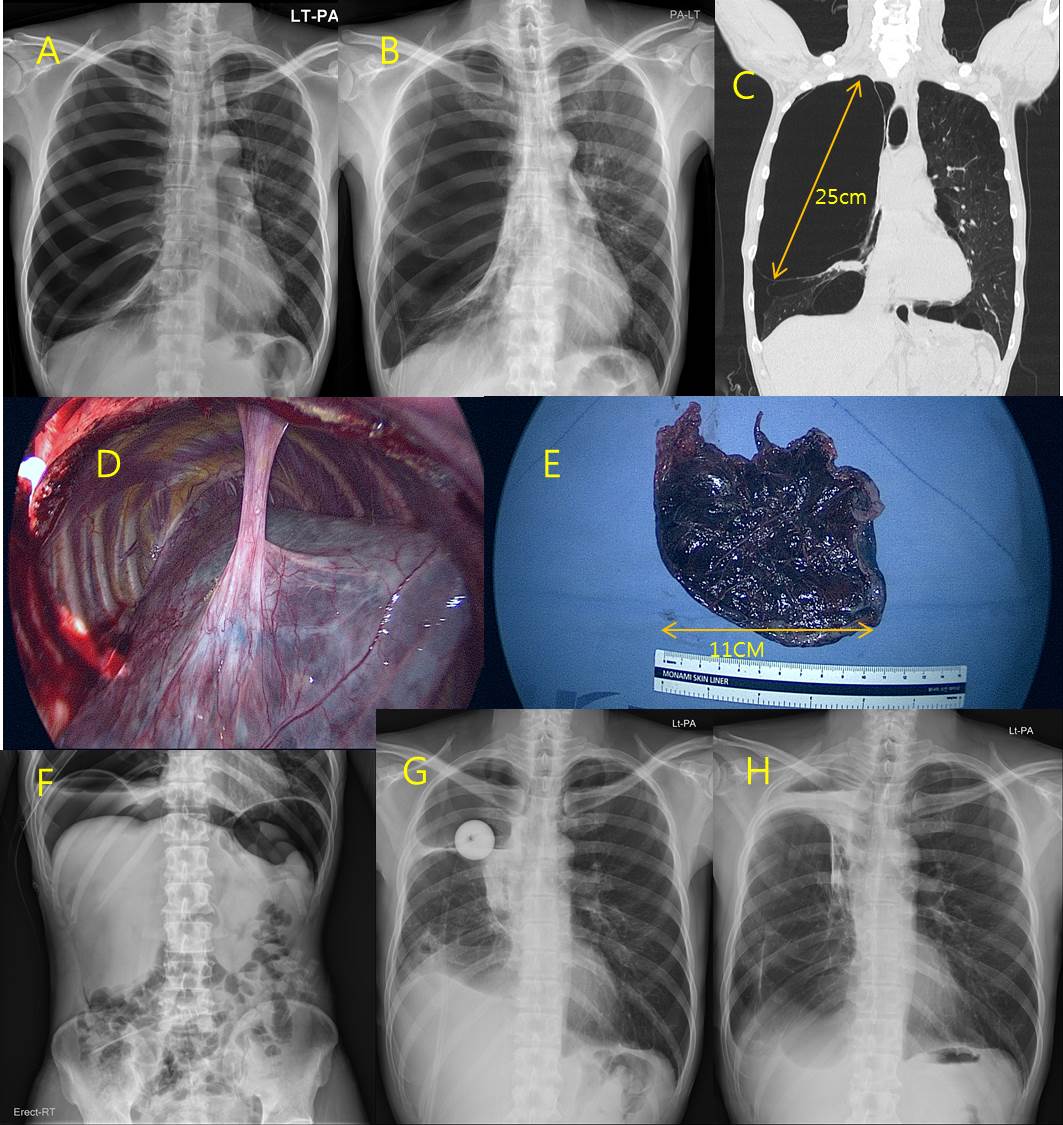

Methods : A 47 years old male chronic smoker was admitted with respiratory distress having history of gradually progressive dyspnea since 3 weeks with productive cough. Chest X-ray showed large lucent areas over the entire right thorax with mediastinal shift to left (Figure A). A Chest tube was inserted under the diagnosis of tension pneumothorax. Follow-up chest radiography showed little expansion of the right lung but restored mediastinum (Figure B). Computed tomography of chest subsequently demonstrated giant bullae occupying the entire right thorax with right lung compressive atelectasis and remnant pneumothorax (Figure C).

Results : The patient underwent bullectomy of right giant bullae by right thoracotomy (Figure D, E). Postoperative air leak was noted and treated with talc pleurodesis, artificial pneumoperitoneum (Figure F) and another closed thoracostomy using foley catheter (Figure G). The patient was in stable condition after 6 month of follow-up (Figure H).